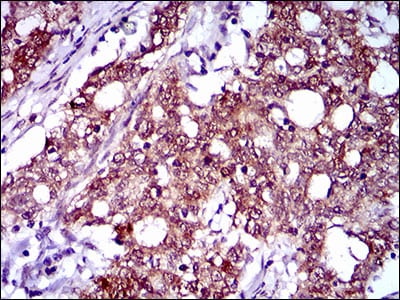

分类: 科研抗体货号: 30534别名: OC3应用: IHC反应种属: Human

分类: 科研抗体货号: 30533别名: OC3应用: IHC,IF反应种属: Human